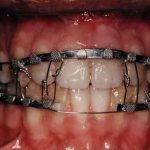

Arch bar

A rigid bar or wire used to stabilize teeth and implants and used for intraarch fixation in the treatment of fractures of the maxilla or mandible.